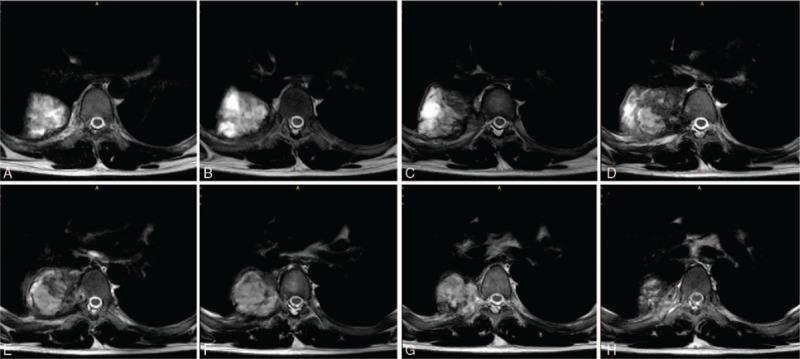

Computed tomography scan and magnetic resonance imaging of spine showed expanding lesion of the T7 vertebral and paraspinal region involving the right thoracic cavity, which presented as a solid tumor. Postoperative pathology confirmed the diagnosis of thoracic benign fibrous histiocytoma.

脊柱计算机断层扫描和磁共振成像显示T7椎体及椎旁区域有一个累及右胸腔的扩大病变,表现为实体瘤。术后病理证实为胸段良性纤维组织细胞瘤。